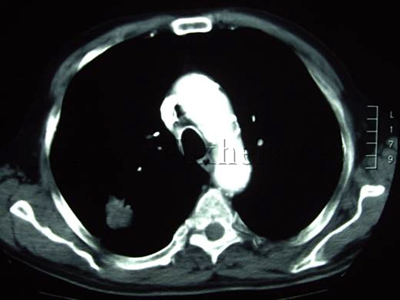

Cáncer de pulmón